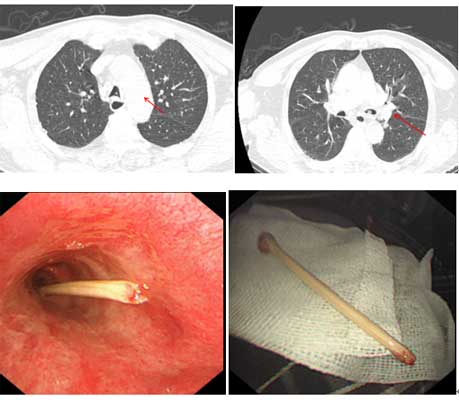

近日,王大爷因棉签断端掉入气道,出现剧烈咳嗽伴轻度呼吸困难,来到北京友谊医院平谷医院急诊科就诊。经了解,王大爷是一位下咽癌术后患者,术后咽喉部有瘘口,平时王大爷自行用长棉签进行瘘口护理。这次不慎将长约5cm棉签断端掉入气道。医生给予患者完善胸部CT检查,结果提示:气管内可见高密度物质嵌顿,考虑异物。医院迅速开通绿色通道,急诊科、呼吸科、内镜室多科联动,决定为患者行气管镜异物取出术。由于棉签断端随着呼吸在气道内上下运动,反复刺激气管粘膜,导致患者出现咳嗽、咯血等症状,情绪变得烦躁不安。时间就是生命,此时患者咳嗽越来越剧烈,必须快速将异物取出,否则随时会有生命危险。医生一边安抚患者,一边将麻醉药物滴入患者气道内,待患者咳嗽稍减轻后,呼吸科与内镜室紧密配合,医生将气管镜迅速送入气道,仔细观察气道内异物嵌顿情况,评估出血风险,用异物钳精准地钳夹住棉签断端,稳准地将异物取出。取出异物后局部仅有少量出血,予以对症处理。术后患者咳嗽、呼吸困难症状明显缓解。